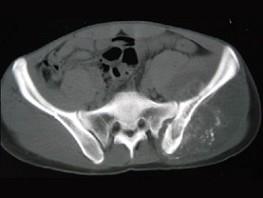

问题 男,35岁,左髂部剧烈疼痛,尤以夜间明显,可摸到肿物,请结合所提供图像,选择最佳选项 ( )

选项 A、骨肉瘤 B、软骨瘤 C、软骨肉瘤 D、骨转移瘤 E、骨巨细胞瘤

答案 A